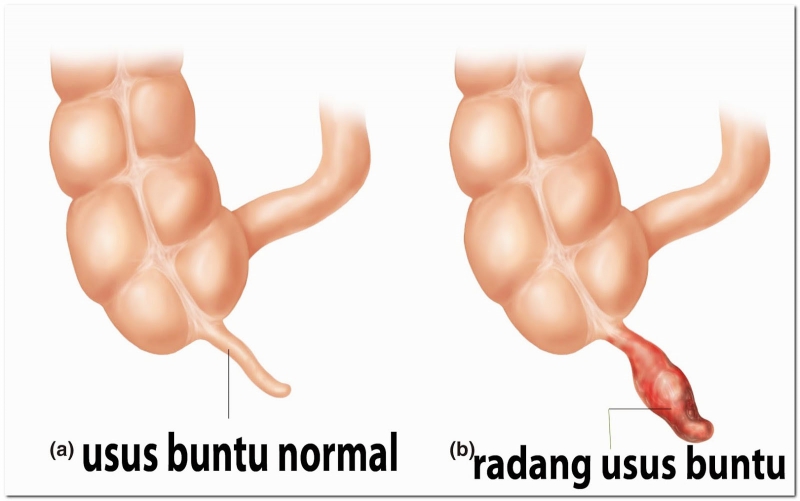

Jangan Diabaikan Karena Dapat Mengancam Jiwa Ini Gejala Usus Buntu Kronis Apa Bedanya Dengan Usus Buntu Akut Semua Halaman Intisari

Jangan Diabaikan Karena Dapat Mengancam Jiwa Ini Gejala Usus Buntu Kronis Apa Bedanya Dengan Usus Buntu Akut Semua Halaman Intisari

Kenali Gejala Usus Buntu Sejak Dini Ini Perbedaan Usus Buntu Kronis Dan Akut Serta Perawatannya Tribunjogja Com

Kenali Gejala Usus Buntu Sejak Dini Ini Perbedaan Usus Buntu Kronis Dan Akut Serta Perawatannya Tribunjogja Com